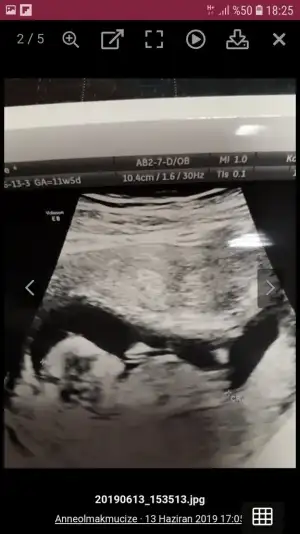

Kizlar cinsiyet tahmininiz varmi dr 12 hafta kiza benzetti 13 hafta baska dr yuzde 55 kiz gibi ama tam goremedim dedi ruyamda oglum olursa adini hamza yilmaz koyucam diyorum hep erkek hissettim ama kizada alistim hayirli saglikli olsun en basta tabiki cuma gunu kontrolum var dr kesinlesir dedi sizin tahminlerinizide alabikirmiyim ilk ikisi 12+digeri 13 haftalik

Eklentiler

• Screenshot_20190630-010258.webp

Screenshot_20190630-010258.webp

17,9 KB · Görüntüleme: 191

• Screenshot_20190704-182556_Samsung Internet.webp

Screenshot_20190704-182556_Samsung Internet.webp

27,1 KB · Görüntüleme: 197

• Screenshot_20190628-223445.webp

Screenshot_20190628-223445.webp

28,8 KB · Görüntüleme: 171